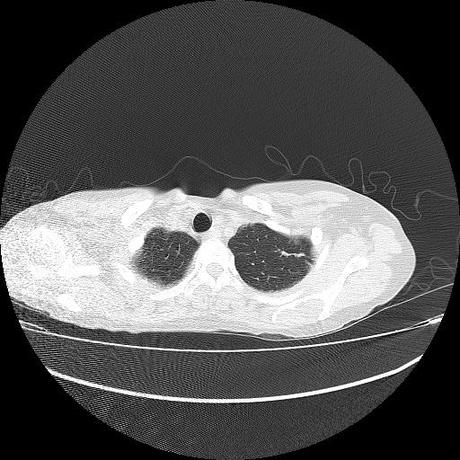

Se realiza volumen de tórax en fase simple, desde los opérculos torácicos hasta los hemidiafragmas, observándose:

El parénquima pulmonar con areas parcheadas difusas en vidrio despulido combinadas con otras areas hipodensas de baja atenuación debidas a atrapamiento aéreo y engrosamiento intersticial y zonas de fibrosis de predominio en lóbulos medios e inferiores de ambos pulmones.

La pleura se encuentra conservada, sin engrosamientos.

- LOS HALLAZGOS PUEDEN ESTAR EN RELACIÓN A NEUMOPATIA INTERSTICIAL PROBABLE ETIOLOGIA HIPERSENSITIVA VS AUTOINMUNE/BACTERIANA/FUNGICA.